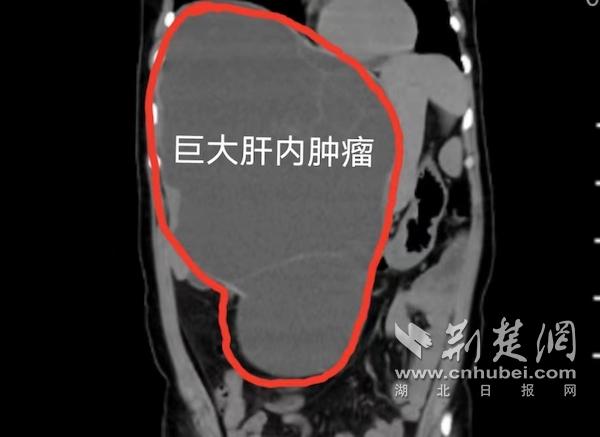

经过检查发现,小周并没有怀孕,而是其腹腔内有一巨大肿瘤。在肝胆胰外科专家门诊,副主任医师孔晓宇详细查体,发现她的肚子鼓鼓囊囊,肿块从胸口一直到肚脐下面,看上去就像怀孕六个多月的孕妇,随后将其收入肝胆胰外科住院。进一步腹部增强CT和核磁共振检查,提示肝脏巨大囊性肿瘤,最大径足足有30厘米,满满占据了整个腹腔,肿瘤将肾脏、十二指肠、胰腺、胆囊等重要脏器推挤移位,同时压迫下腔静脉、腹主动脉等重要血管。

巨大肝内肿瘤。通讯员供图